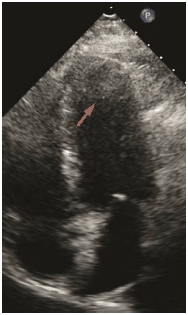

Marque a alternativa que apresenta o artefato representado na imagem abaixo (seta).

Marque a alternativa que apresenta o artefato representado na imagem abaixo (seta).